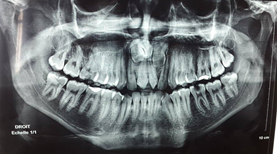

A panoramic radiograph (Figure 2) revealed the presence of two impacted teeth in the anterior region.

Figure 2 Panoramic radiograph.